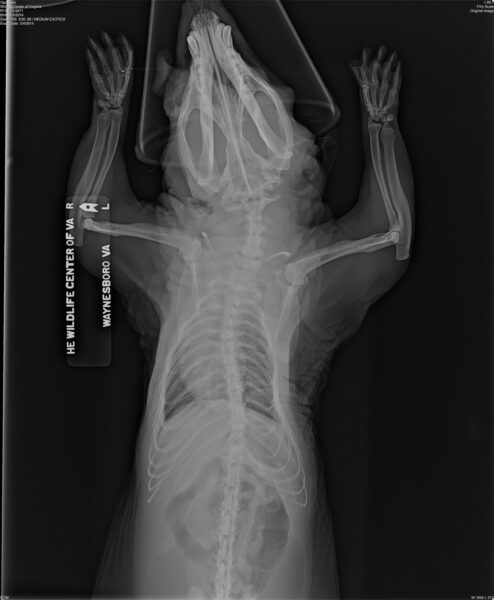

Cette radiographie d'un opossum gardé en captivité montre des anomalies osseuses - courbure des pattes et de la colonne vertébrale - qui se produisent souvent lorsque les animaux captifs sont nourris de manière inappropriée par des personnes non formées. Avec l'aimable autorisation du Wildlife Center of Virginia